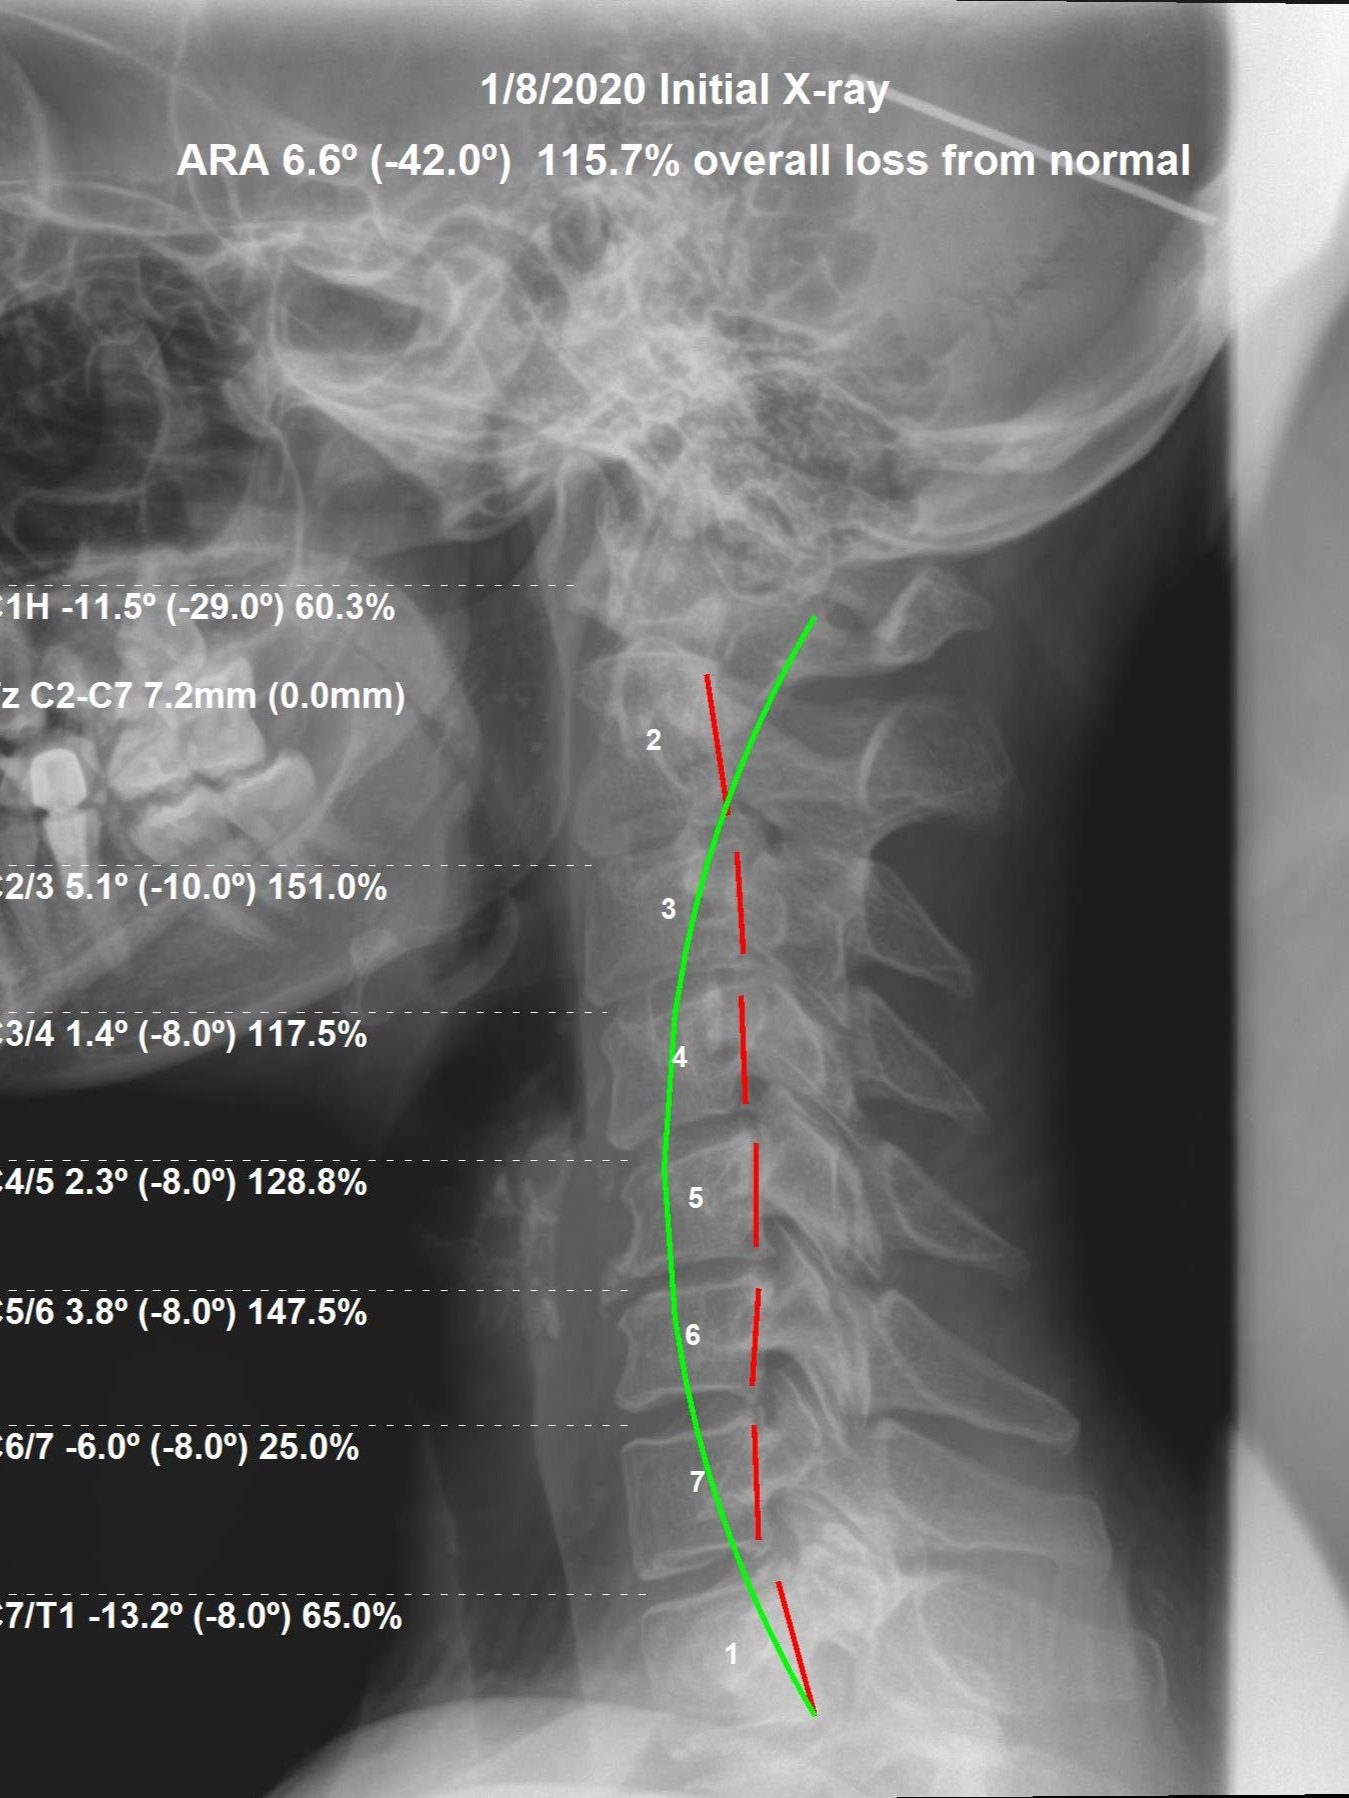

Correction of the Month